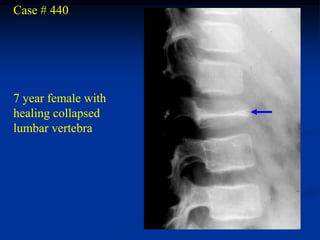

Case # 440

7 year female with

healing collapsed

lumbar vertebra